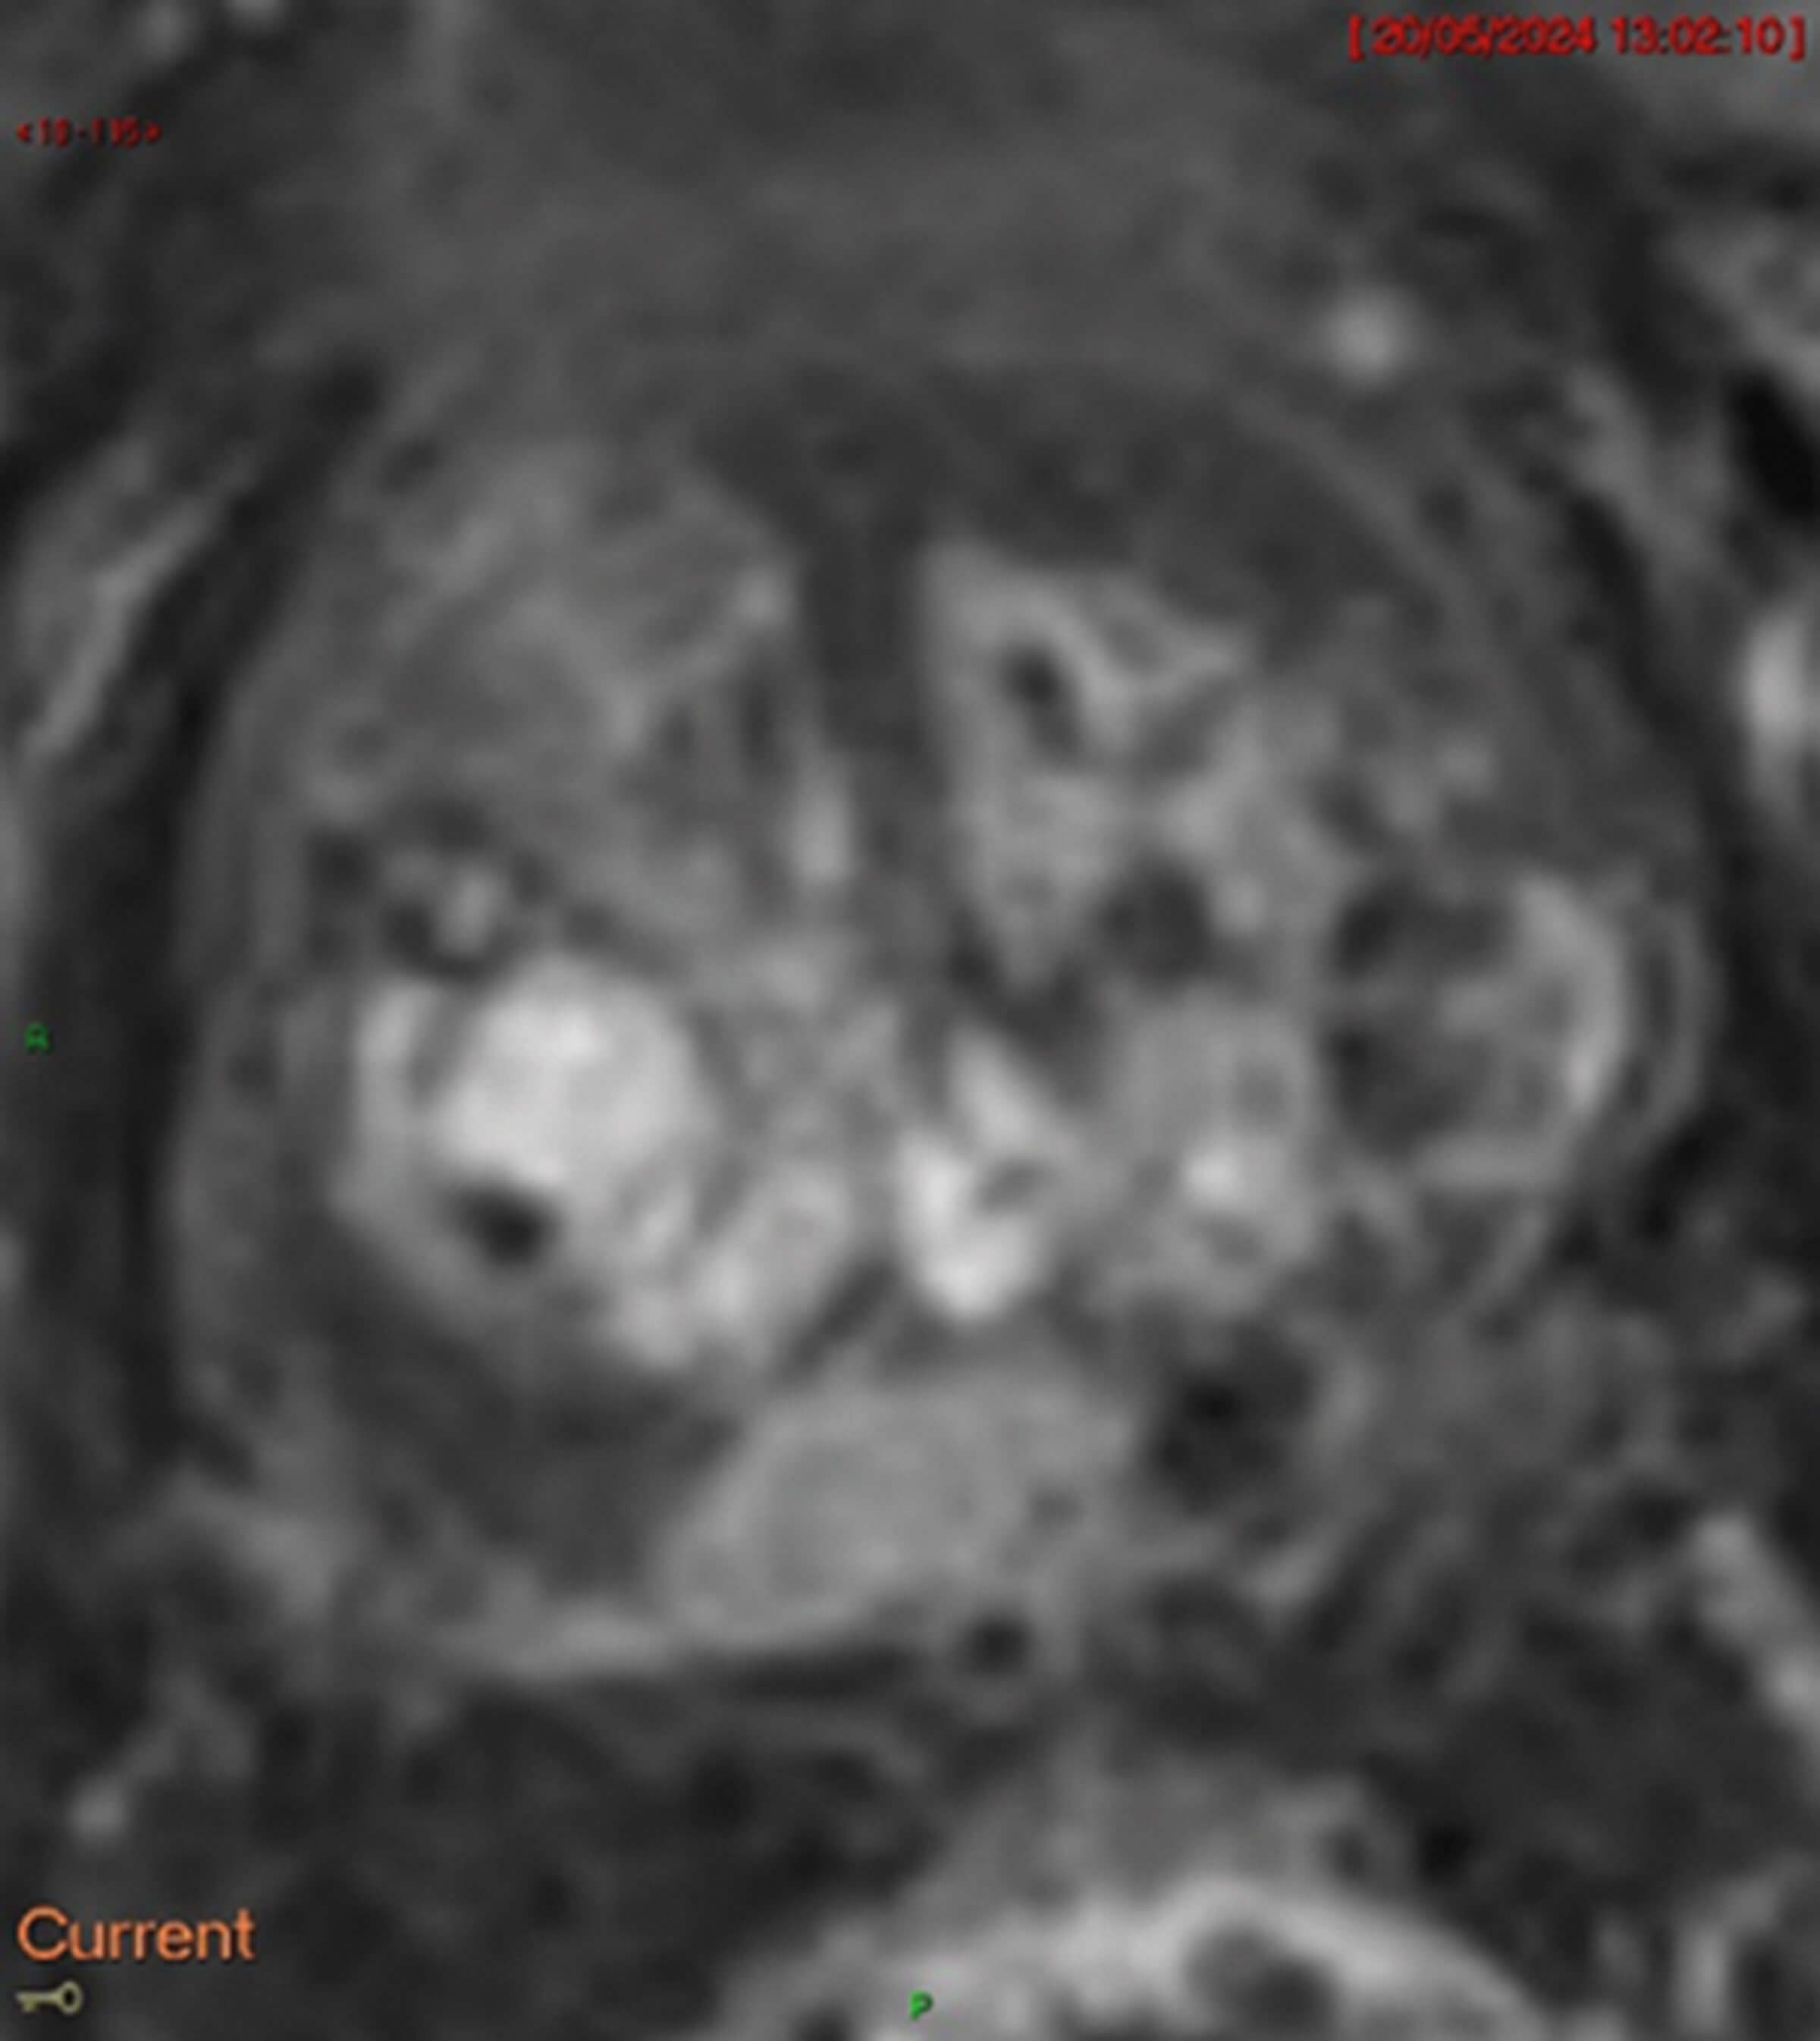

Figure 4.

- Figures 2-4 are the different MRI sequences. What sequences are they and what do they represent?

Dynamic contrast enhancement (DCE, Figure 4) completes the multi-parametric MRI (mp-MRI) sequence. Without DCE, it is termed bi-parametric MRI (bp-MRI). DCE assesses tissue enhancement after Gadolinium contrast administration, exploiting tumour neoangiogenesis and abnormal vessel leakage which cause contrast stasis in tumour regions and appear as enhancement.